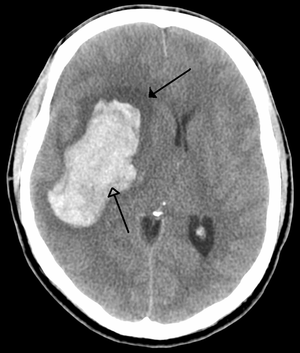

An intraparenchymal bleed (bottom arrow) with surrounding edema (top arrow)

A CT showing early signs of a middle cerebral artery stroke with loss of definition of the gyri and grey white boundary